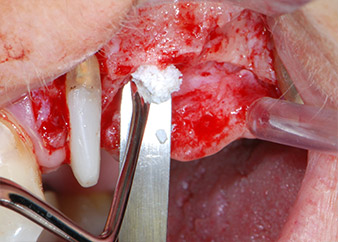

Vor der Insertion der Implantate wurde infiziertes Weichgewebe im Implantationsbereich und um das Abutment mit einem Instrument entfernt, das laut Hersteller primär zur Knochenbearbeitung und zum Sammeln von Knochenspänen vorgesehen ist (Piezomed, Einsatz B5) (Abb. 6 und 7).